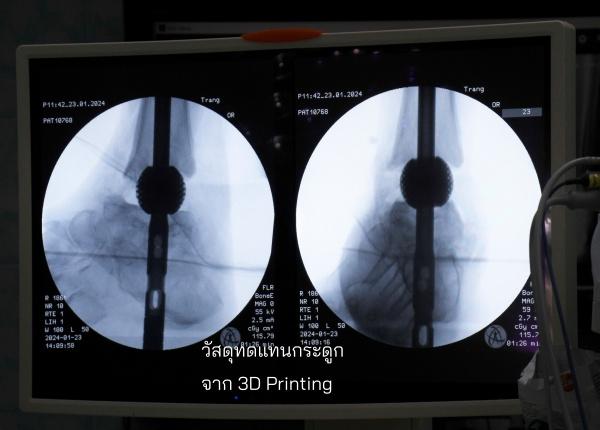

งานวิจัย มจธ. สุดล้ำ ใช้เทคโนโลยีพิมพ์สามมิติ สร้างวัสดุทดแทนกระดูกพรุน ออกแบบเฉพาะบุคคล พลิกโฉมการรักษาผู้ป่วยโรคกระดูกและการศัลยกรรมขากรรไกร รุกจดสิทธิบัตรส่งขายตลาดโลก

มหาวิทยาลัยเทคโนโลยีพระจอมเกล้าธนบุรี (มจธ.)  เปิดตัวนวัตกรรมวัสดุทดแทนกระดูกพรุนพิมพ์ด้วยเทคโนโลยีสามมิติ จากการออกแบบโครงสร้างวัสดุพรุนจากกระบวนการพิมพ์สามมิติ เพิ่มคุณสมบัติเชิงกลและเชิงชีวภาพสำหรับเป็นวัสดุทดแทนกระดูก พัฒนาระบบวางแผนการผ่าตัดแบบดิจิทัลและกระดูกเทียมเฉพาะบุคคล สำหรับศัลยกรรมกระดูกและใบหน้า ด้วยเทคโนโลยีการพิมพ์สามมิติและปัญญาประดิษฐ์ (Artificial Intelligence: AI) พัฒนาโดยทีมวิจัย มีรศ. ดร.พชรพิชญ์ พรหมอุปถัมภ์ อาจารย์ภาควิชาวิศวกรรมเครื่องกล คณะวิศวกรรมศาสตร์ มหาวิทยาลัยเทคโนโลยีพระจอมเกล้าธนบุรี (มจธ.) และ ผู้บริหารระดับสูงด้านเทคโนโลยีและนวัตกรรม (Chief Technology Officer : CTO) บริษัท ออสซีโอแล็บส์ จำกัด ธุรกิจที่แยกตัว (Spin-off) ของ มจธ. เป็นหัวหน้าโครงการฯ เป็นการบุกเบิกในวงการศัลยกรรมกระดูก นวัตกรรม เพื่อแก้ไขข้อจำกัดการรักษาแบบดั้งเดิม โดยเฉพาะปัญหาการติดเชื้อซ้ำสูง ช่วยให้กระดูกของผู้ป่วยยึดติดกันได้ดี มีความแม่นยำทางกายวิภาคของวัสดุทดแทนกระดูกที่ใช้กันทั่วไปจากเดิมที่ใช้ กระดูกบริจาคหรือซีเมนต์ทางการแพทย์

จุดเด่นของนวัตกรรม คือKnow-how การออกแบบกระดูกเทียมเฉพาะบุคคลให้เป็นอุปกรณ์ทางการแพทย์ที่ใช้งานได้ดี เหมาะสมกับแผนการรักษาที่แพทย์วางไว้และใช้งานได้จริง ประกอบกับโครงสร้างวัสดุพรุนที่ทำจาก 3D Printing เป็นตัวเข้ามาเสริมการเกาะของกระดูก เข้าใจ Pain Point ของแพทย์